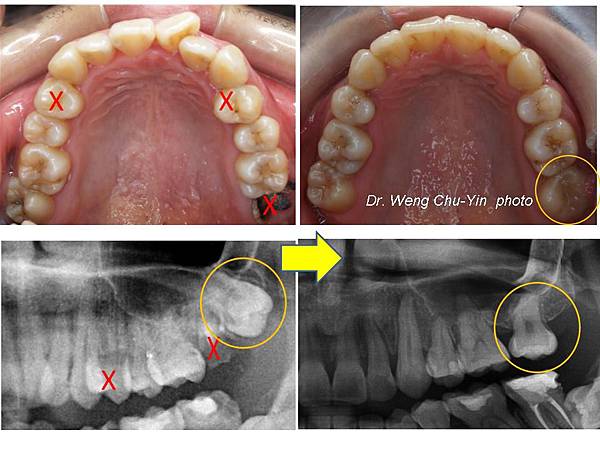

缺牙病例 矯正立正智齒 關閉大臼齒空隙 矯正專科翁竹音醫師 矯正專科 翁竹音醫師 痞客邦